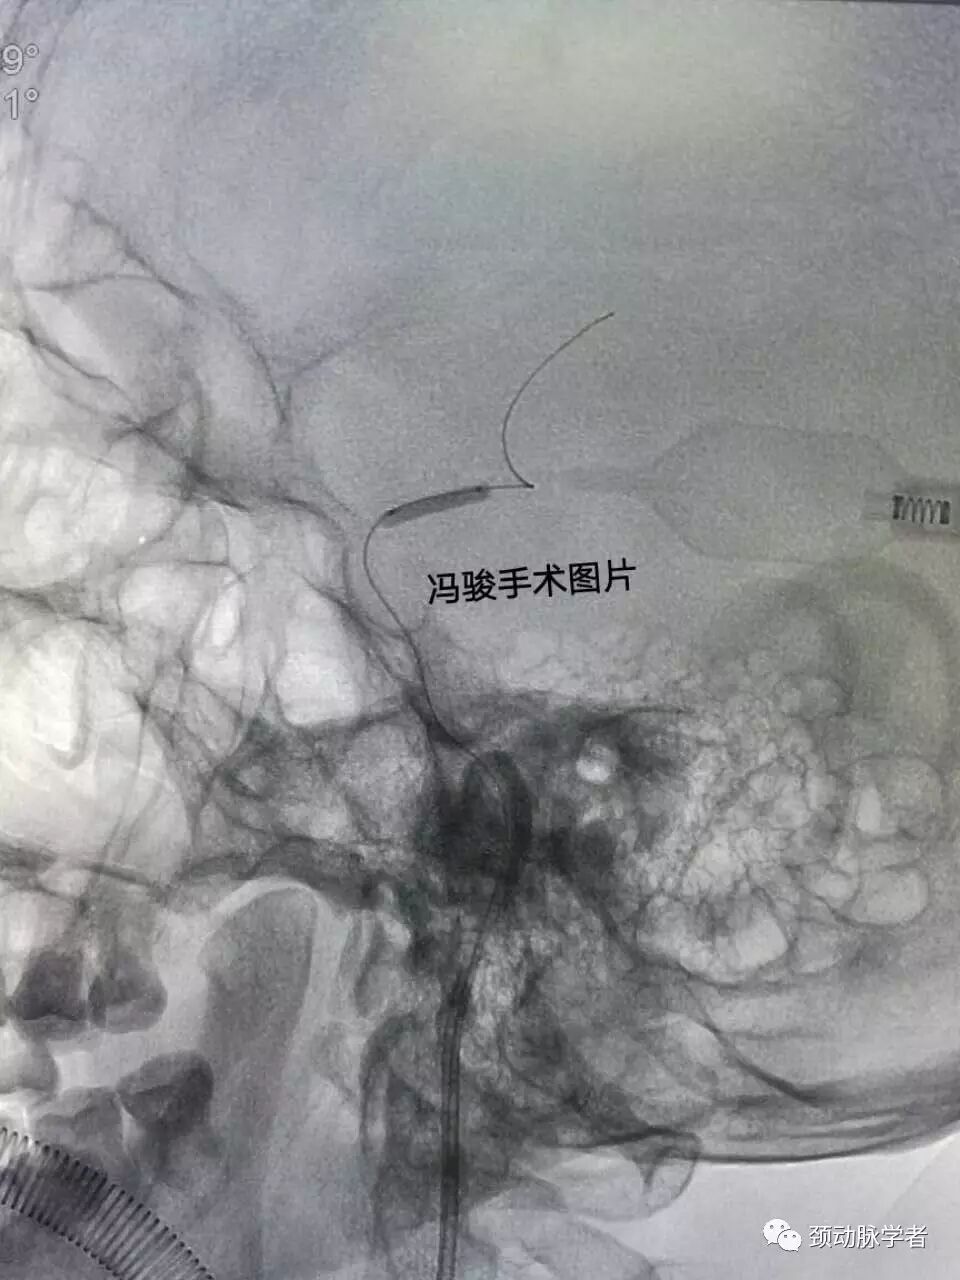

全麻下,guiding置入左颈内动脉海绵窦,造影显示,床突上段的确99%线样狭窄。

球囊预扩后,病变处狭窄改善,但又有弹性回缩。看来必须置入支架了,既要解除狭窄,又不能影响病变近远端分支血管,需要极高的准确性。

精准定位后,释放2.5-8mm,apollo支架,再次造影显示,狭窄解除,血流通畅。